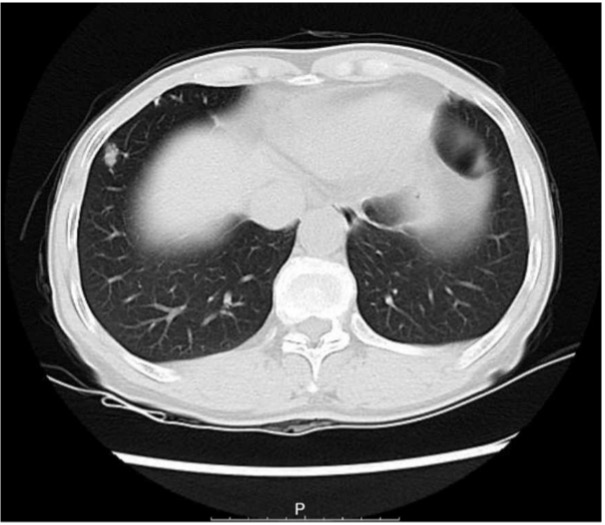

The efficacy of Celnovte Biotechnology’s frozen section rapid IHC technology can be observed in the following case study. In this example, doctors in China cite an example of lung cancer where rapid IHC was used. The patient, a 67-year-old female, was admitted to the hospital and underwent surgical treatment due to nodules seen in a CT scan that were not responsive to anti-inflammatory treatment.

Figure 1 – CT scan of patient in case study 1, the bilateral thorax was symmetrical, and no obvious abnormalities were found. The trachea is centered, and the tracheobronchial tree is unobstructed. A solid nodule (thin layer lm373) was found in the lower lobe of the right lung, with a long diameter of approximately 11.3 mm. There are a few micronodules in both lungs. The structure of the bilateral lung hilum was clear, and there were no obvious abnormalities in shape, size, and position. There was no abnormal enlargement of lymph nodes in each group of mediastina.